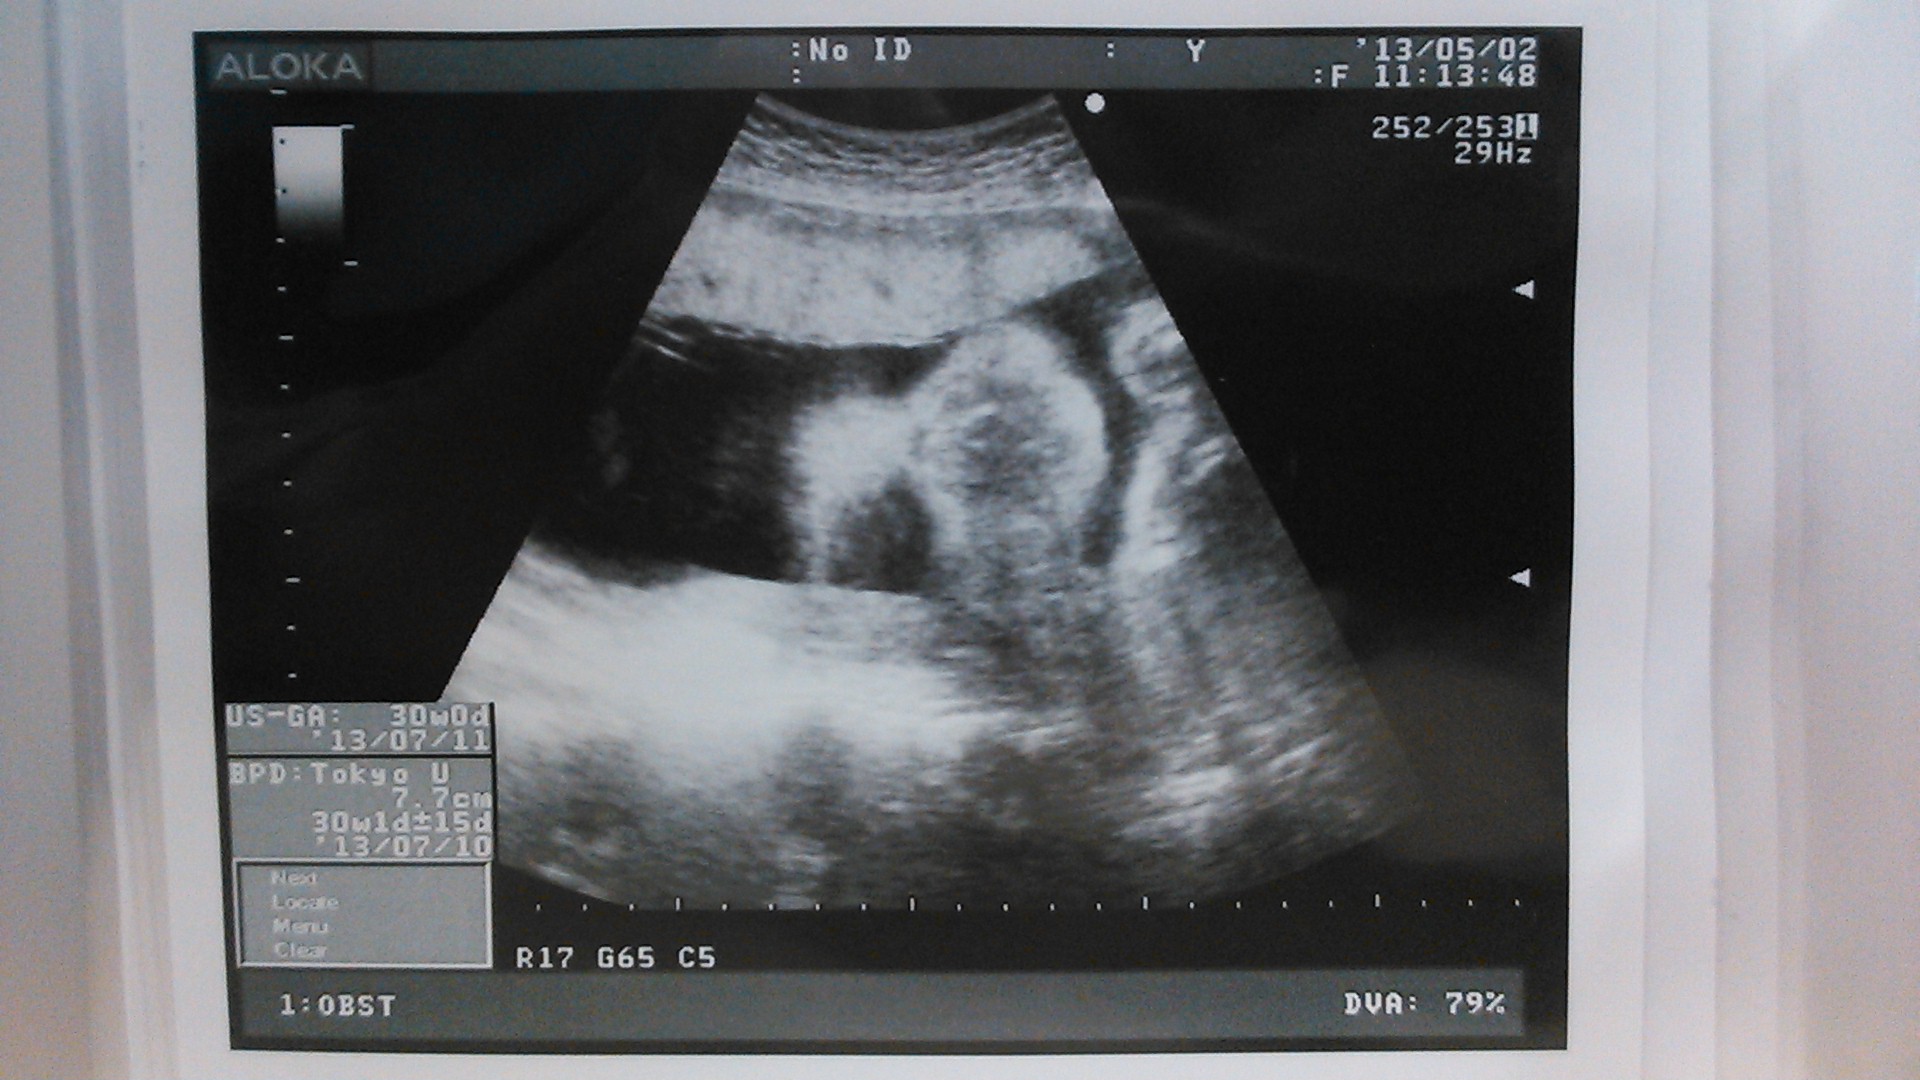

echo